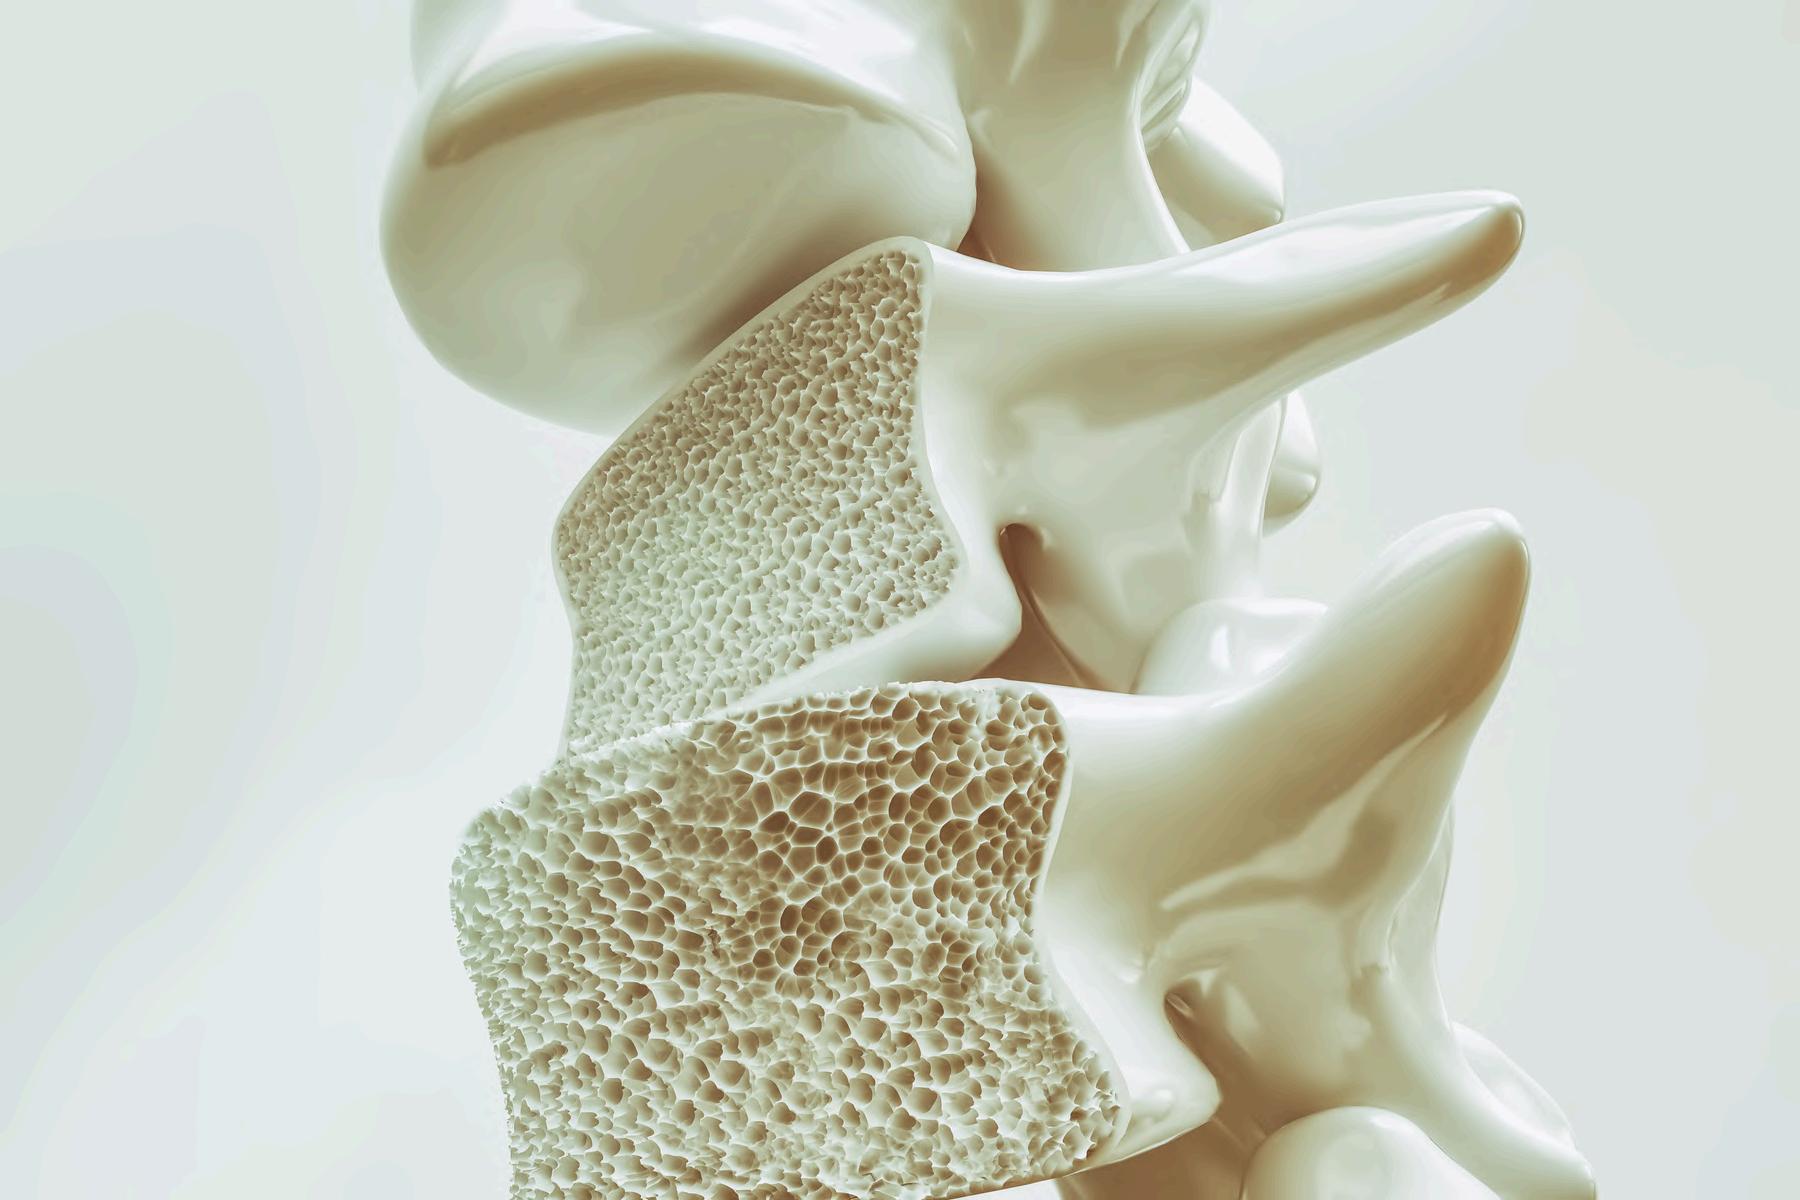

El Dr Isaac Cervantes, por su parte, nos habla de la osteoporosis, una enfermedad que muchas veces avanza sin síntomas visibles pero que debilita progresivamente los huesos, convirtiéndose en un problema cada vez más frecuente en la población